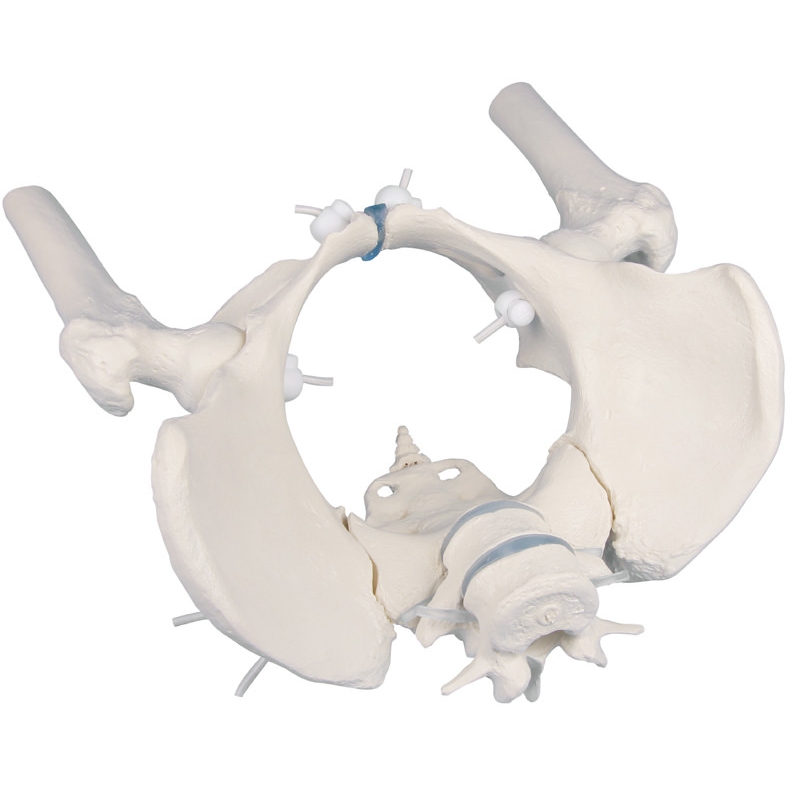

Ženska medenica s križnico, dvema ledvenima vretencema in stegnenico, gibljiva

Naravni odlitek medenice odrasle ženske Medenico je mogoče hitro in enostavno razstaviti. V celoti je pritrjena z gumijastimi trakovi, ki omogočajo izjemno gibanje. S fleksibilno pritrjenima L5 in L4. Stegnenični peclji so premični in odstranljivi.